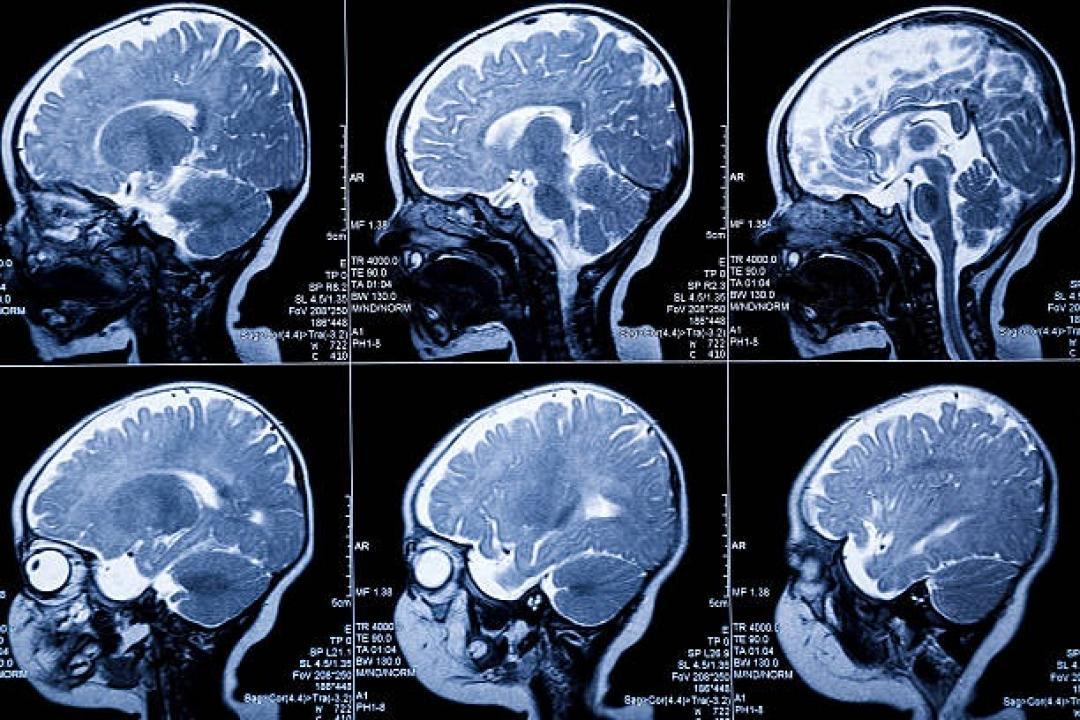

પ્રતીકાત્મક તસવીર (સૌજન્ય : આઇસ્ટૉક)

ચીનમાં ન્યૂરોલૉજી જર્નલમાં પ્રકાશિત એક સમાચાર પ્રમાણે તેમાં કહેવામાં આવ્યું છે કે ચીનમાં એક વર્ષ પહેલા પેદા થનારી બાળકીના મગજમાંથી એક ભ્રૂણ કાઢાવમાં આવ્યું છે. કહેવામાં આવી રહ્યું છે કે જન્મ લીધા પછી બાળકીના મગજની સાઈઝ ખૂબ જ ઝડપથી વધી રહી હતી. જેથી ચિંતામાં આવીને તેના માતા-પિતા તેની સારવાર માટે તેને હૉસ્પિટલમાં લઈ ગયાય ત્યાં તે બાળકીના મગજનું સિટી સ્કેન કરવામાં આવ્યું તો આ ભેદ પરથી પડદો ઉઠ્યો.

બાળકીના મગજના સિટી સ્કેનના રિપૉર્ટની તપાસ કરતા ડૉક્ટર્સે તેના મગજમાં એક ભ્રૂણ જોયું. જેને જોઈને ડૉક્ટરસની ટીમ પણ ચોંકી ઊઠીં. એક રિપૉર્ટ પ્રમાણે ડૉક્ટર્સે જણાવ્યું કે બાળકીના મગજની અંદર ભ્રૂણ લગભગ 4 ઈન્ચ સુધી વધી ગયું હતું. જ્યાં તેની કમરના હાડકાં અને આંગળીઓના નખનો વિકાસ થઈ ગયો હતો. આ એક લાંબા અને સફળ ઑપરેશન બાદ બાળકીના મગજમાંથી તે ભ્રૂણને બાળકીના મગજમાંથી બહાર કાઢી લેવામાં આવ્યું છે.